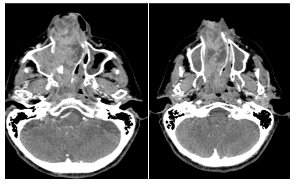

En la Tomografía sin contraste del macizo cráneo facial se aprecia formación de densidad de partes blandas ubicada en fosa nasal y seno maxilar derecho con extensión a senos frontales y celdillas etmoidales, la formación hace protrusión hacia las coanas y Cavum con marcado realce postcontraste (Figura 3).

En la ventana ósea se destacan signos de marcada remodelación ósea predominantemente de los senos maxilar derecho y fosa nasal (Figura 4).

Se considera que las estructuras óseas encontradas se deben a restos de celdillas etmoidales y cornetes embebidos en el seno de la masa tumoral. “La localización en zonas como el seno frontal, las celdillas etmoidales supraorbitarias o la región periorbitaria, contraindican la cirugía por vía endoscópica” (Bernardo, Hernández, Calvo, Llorente, & Gómez, 2001); (Aderito, Urdaneta Lafée, Abreu-Durán, & Rodríguez-Hernández, 2017).